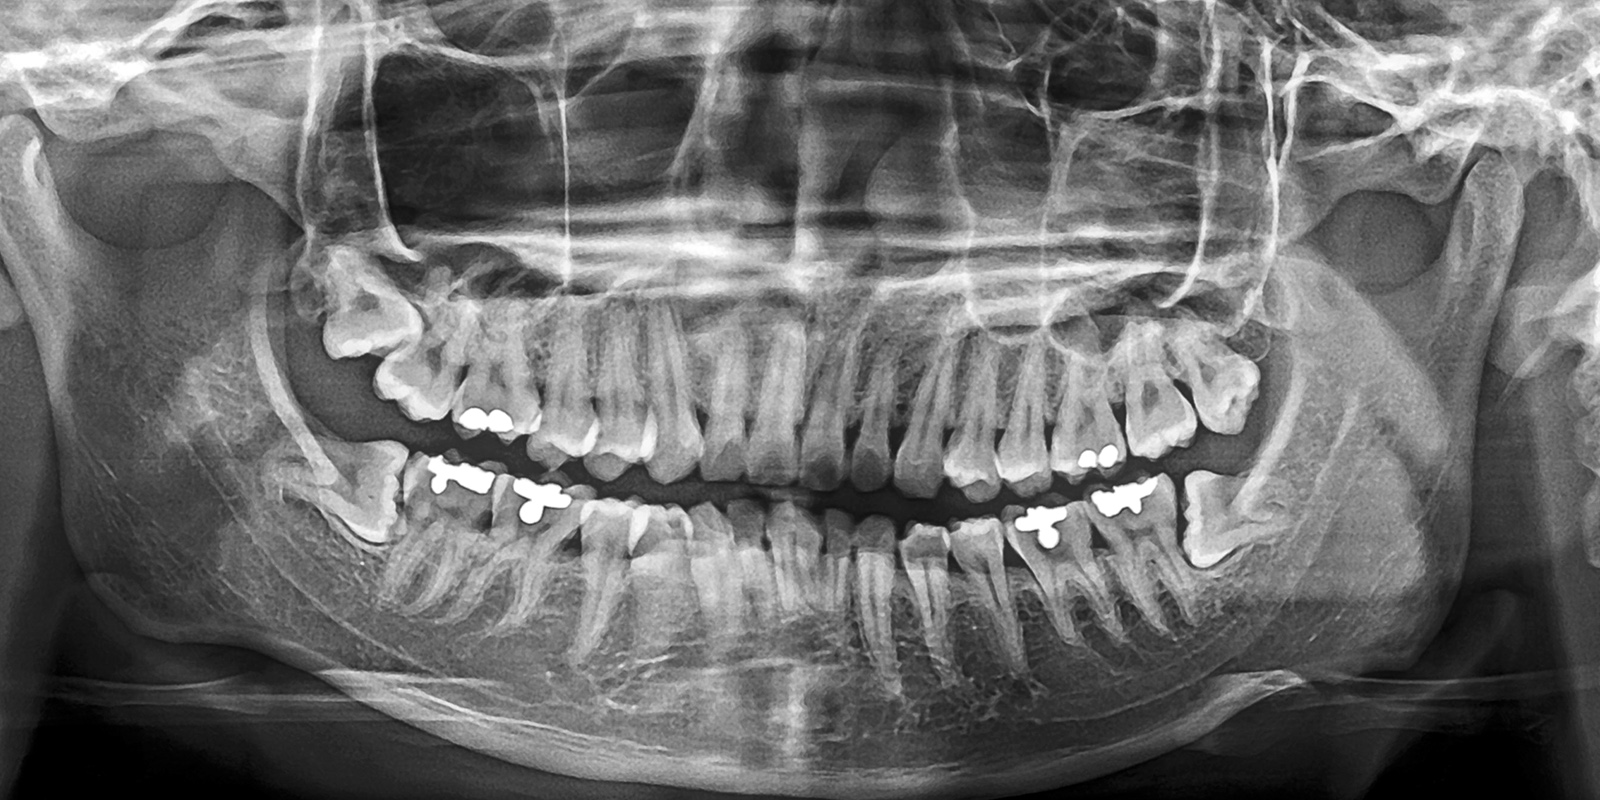

パノラマレントゲンの活用

パノラマレントゲンは、お口全体を1枚の画像として撮影できる広範囲のレントゲン写真です。これにより、親知らずの位置や向き、そして周囲の歯との関係がひと目でわかります。

特に下あごの親知らずは、下歯槽神経という大事な神経の近くにあることが多いため、抜歯時の神経損傷リスクを回避することが非常に重要です。パノラマ撮影を行うことで、神経との距離や重なり具合を正確に確認することができます。